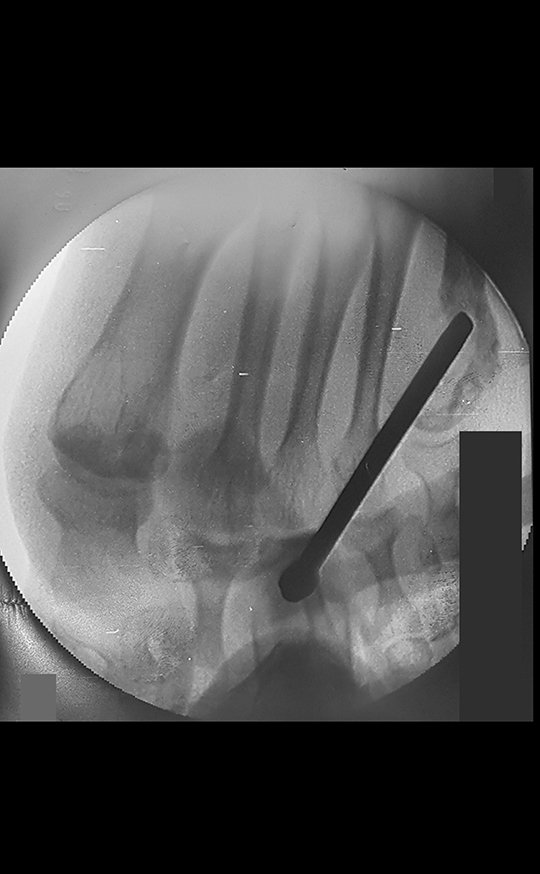

Fibroma desmoide del pie. Paciente de 43 años con “callo” en el quinto metatarsiano del pie izquierdo desde hace veinte años, que desarrolló deformidad, aumento de volumen y dolor en el último año.